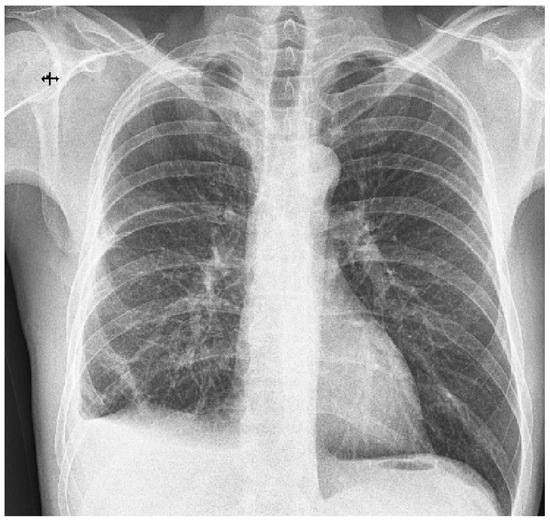

Sequence of Rare Diagnoses in a Young Patient: Altitude Barotrauma Hemopneumothorax and Desquamative Interstitial Pneumonia

Leonte, I.; Ivanov, K.; Marghescu, A.Ș.; Matache, Ș.R.; Negru, F.V.; Iorga, A.L.; Dumitru, S.M.; Mahler, B. Sequence of Rare Diagnoses in a Young Patient: Altitude Barotrauma Hemopneumothorax and Desquamative Interstitial Pneumonia. Diagnostics 2023, 13, 2367. https://doi.org/10.3390/diagnostics13142367